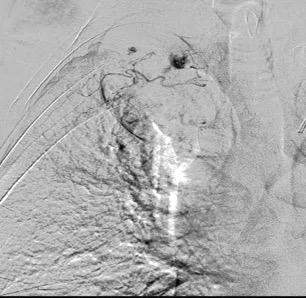

Paraganglioma

Aneurisma de arteria bronquial

3% segregan catecolaminas.

(En el área Paravertebral +/-50%.)

Intenso realce con el contraste.

32 años .Preeclampsia a los 19. Hipertensión no controlada. Masa paravertebral sólida que se realza intensamente con afectación ósea.

Yue Y t al. Asymptomatic left posterior mediastinal functional Paraganglioma. A case report. Medicine . 2019